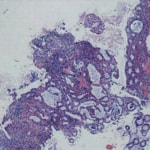

病理検査:直腸の病変は、良性の非腫瘍性病変の一つである“炎症性ポリープ”と診断された。

診断後経過:炎症性ポリープは多発する傾向や腫瘍に転化する可能性があるため、消炎剤、抗生剤、整腸剤による内科療法を継続しながら、現在プルスルー法による外科的摘出術を検討中。

◎炎症性ポリープとは

近年、ミニチュアダックスで好発が知られている良性の腫瘍性の病変です。しばしば多発し、また腫瘍に転化する事があります。